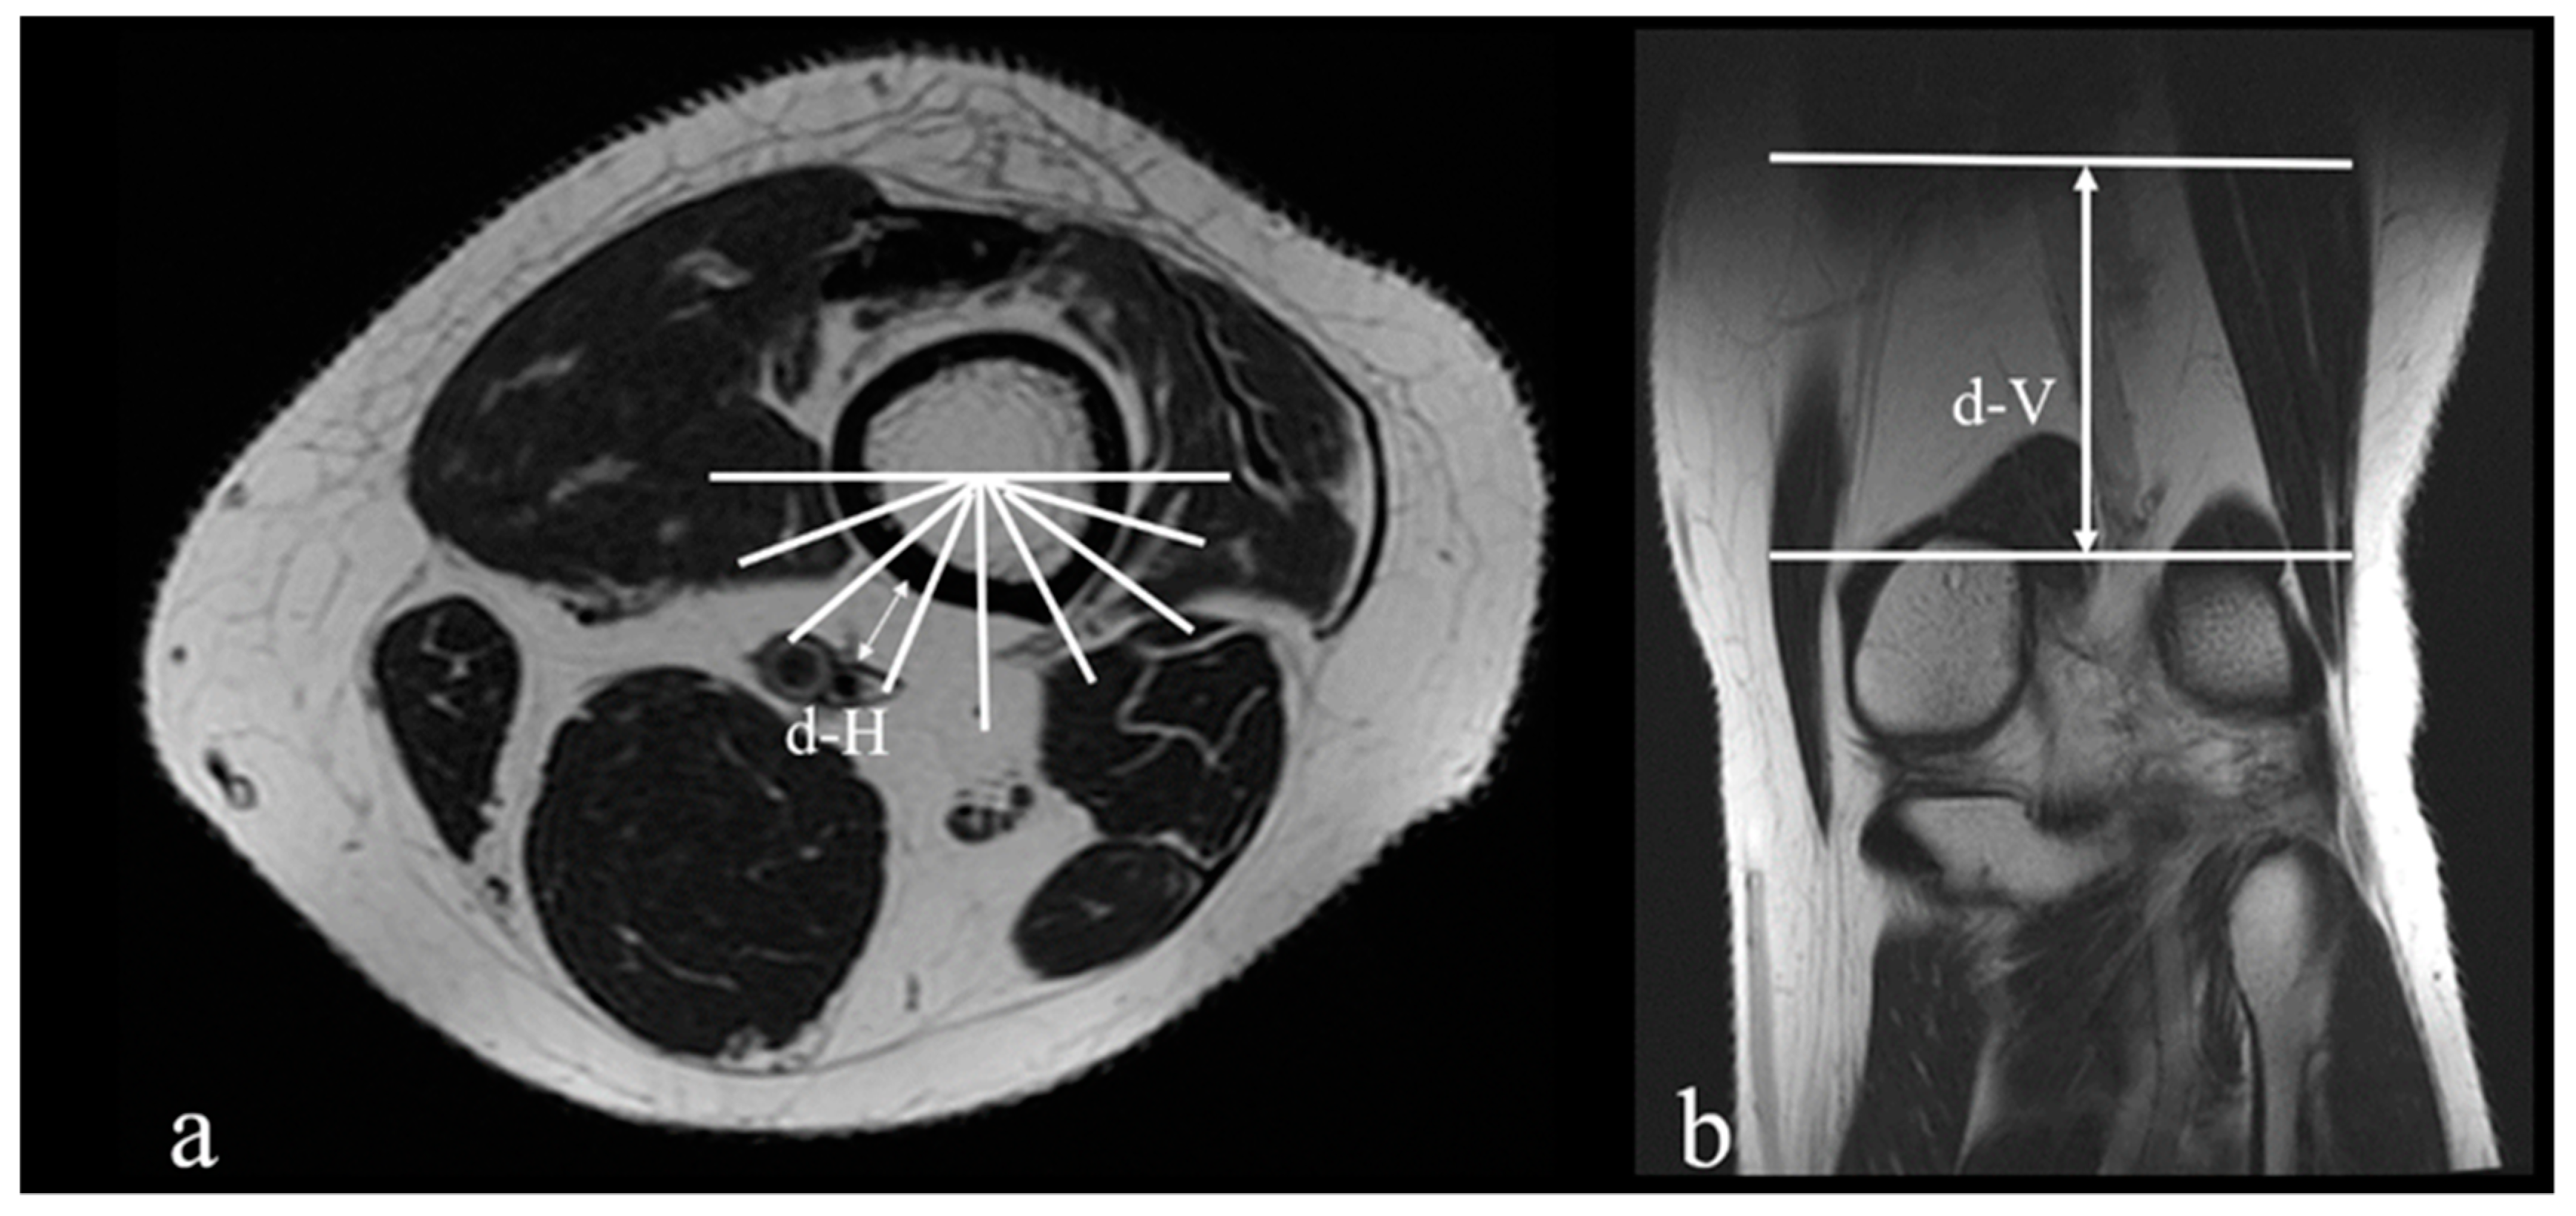

| d-H (mm) | 7.92 ± 3.42 | 6.76 ± 2.86 | 0.010 |

| d-V (mm) | 61.79 ± 9.39 | 51.54 ± 10.49 | <0.001 |